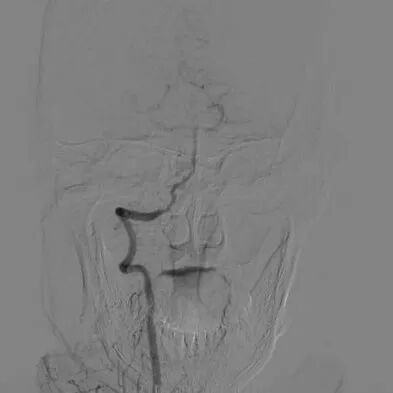

心脑联合造影

-- 左侧颈内起始部重度狭窄